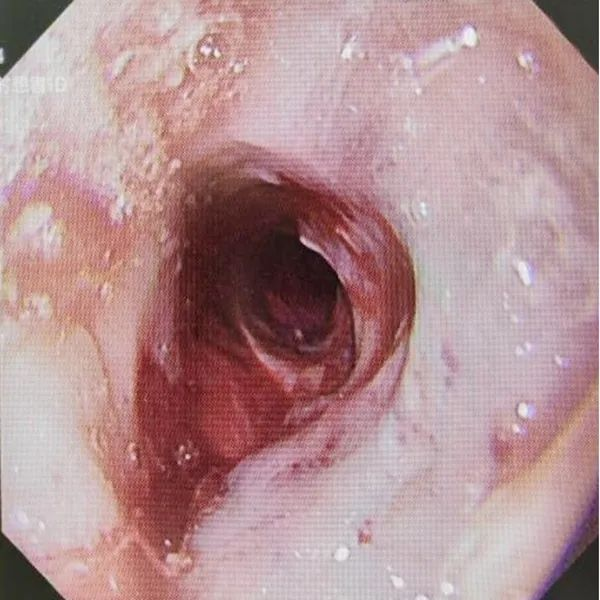

▲球囊扩张治疗后,扩张口大于1cm

两年前赖阿姨因腐蚀性食管炎造成食管狭窄,曾置入食管覆膜支架,但近期吞咽困难加重,吃流食也很难下咽,吃一顿稀饭需近一个小时,消化内科郑中文主任为该患者进行胃镜检查,发现进镜距门齿28-29厘米处食管腔呈环形向心性狭窄,直径仅约3-4毫米,内镜无法通过。经过综合评估,决定为其行内镜下球囊扩术。手术过程中,通过内镜活检钳道送入球囊扩张导管至狭窄段,注入生理盐水使球囊扩张,以4-8ATM(1ATM=101.325 kPa)的压力分次加压扩张,每次持续约1-2分钟,逐渐扩张狭窄食道。术后患者吞咽困难症状明显改善,无明显并发症表现,已于近日康复出院。